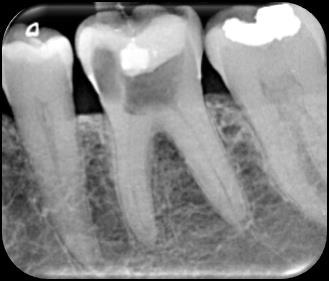

Dr. Dhiraj Arora: A Simple Sequence for Successful Root Canal Treatment Outcomes (DE)